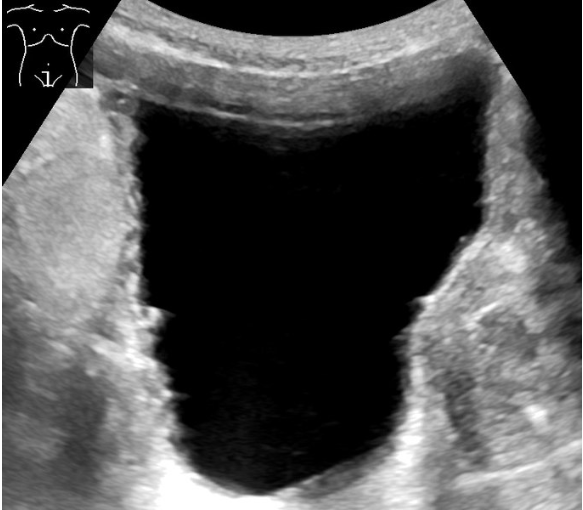

- US KUB scan if suspect high pressure retention to look for hydronephrosis

- Other imaging: AXR with IV urogram (most stones not radiolucent and high radiation exposure) or US to assess for hydronephrosis